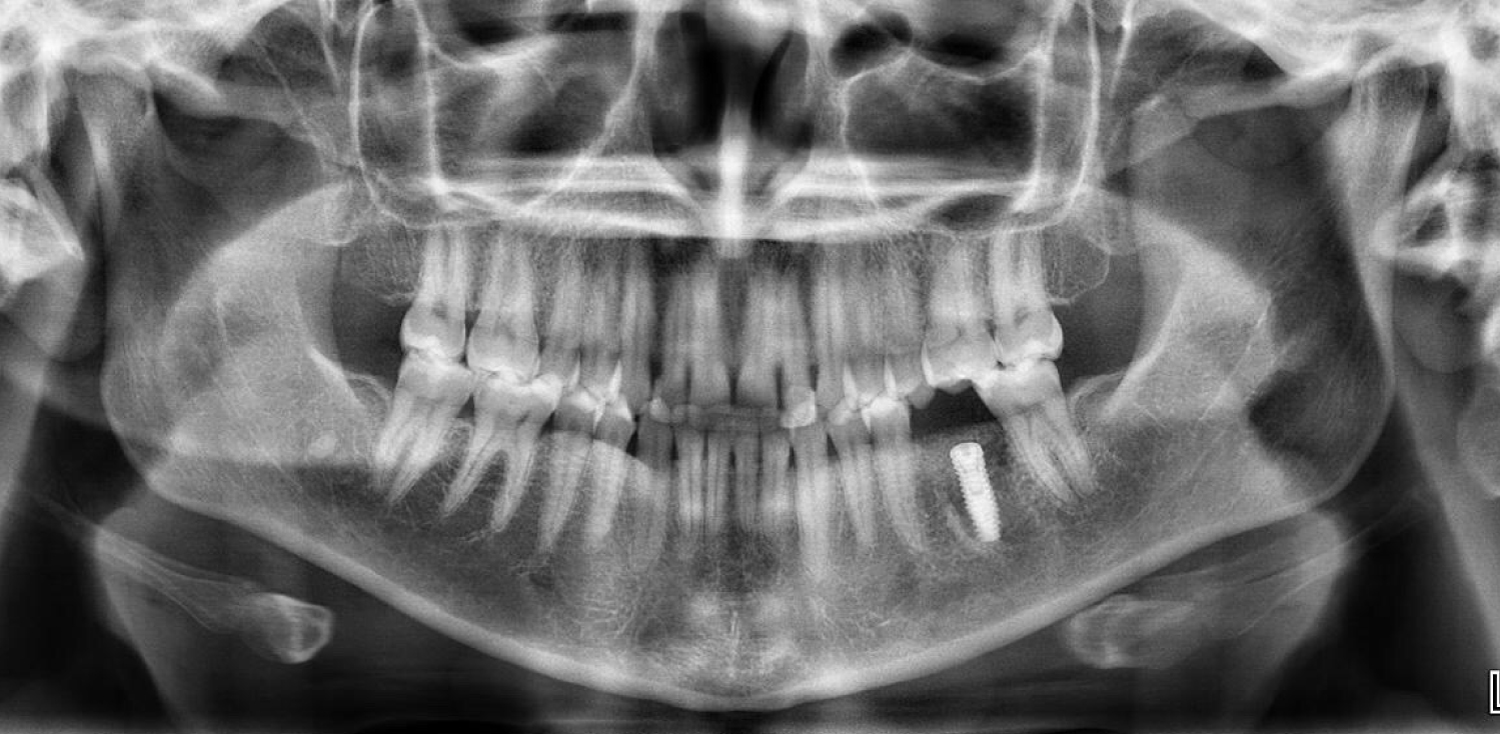

A 29-year-old female patient attended the Oral and Maxillofacial Surgery Unit of University Hospital of Maracaibo, Venezuela, presenting pain in the posterior left mandibular region. Her medical record was unremarkable. On clinical examination, the inferior left first molar (#36) presented with endodontic treatment which had been performed in two previous opportunities due to the persistence of associated pain on vertical and transversal percussion. A panoramic X-ray was requested, and the endodontic treatment with a partially fractured crown was observed in the aforementioned tooth, with no radiolucent images associated (Figure 1). Due to these findings, the final diagnosis of cracked tooth syndrome was decided and thus, the treatment plan chosen was to extract the tooth and place an implant using a surgical guide in the same surgery along with guided bone regeneration. The patient's mandibular cast was scanned using an extraoral scanner (Ceramill Map 300, Amann Girrbach, Austria) (Figure 2) and the STL file was obtained and edited in order to eliminate the crown of the tooth using MeshMixer program (Autodesk, Canada) (Figure 3). The edited denture scan was aligned to the mandibular CBCT scan of the patient in Blue Sky Plan (Blue Sky Bio, USA) to allow for prosthetically driven implant planning. Implant placement simulation was carried out in the software aiming for the site with the most surrounding bone while being prosthetically acceptable (Figure 4) and a surgical guide was designed and printed in a desktop 3D printer (AnyCubic Photon, China) (Figure 5 and Figure 6). Under moderate sedation and local anesthesia, the molar was a traumatically extracted, the surgical guide was held in position (Figure 7) and a 4.0 × 13 mm IS II active implant (NeoBiotech, Korea) was placed using the NeoBiotech Naviguide system. Subsequently, the alveolar gaps were filled using cortico-cancellous bone allograft (Ossogen, Lattice Biologics, USA) (Figure 8) and two Platelet-Rich Fibrin (PRF) membranes made using the protocol described by Choukroun [6] (Figure 9). Simple sutures using 3-0 polyglactin 910 (Vicryl, Ethicon, USA) were used for closure.

Figure 1: Preoperative panoramic x-ray. View Figure 1

In the seventh postoperative day, the patient referred an uneventful course, with minimal pain and swelling. A panoramic X-ray was obtained where the correct placement, angulation and depth of the implant could be observed (Figure 10).

Figure 10: Postoperative panoramic x-ray showing the correct position of the implant after 7 days. View Figure 10